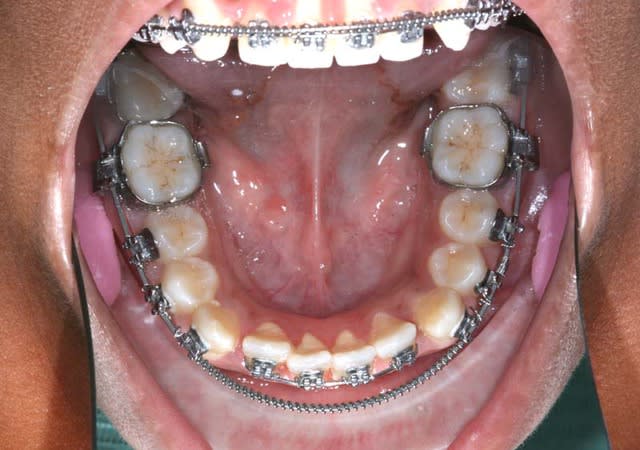

Sur la photo précedente, on est en 16*x16* à mémoire de forme et en friction Damon

j’ai Tjs. un Pb. de rotation sur les Inc. Inf.

aussi j’ai changé les Bk . céramique Inf. pour des Bk. titane, qui ont meilleure glisse, j’ai mis un ressort de Root (D gainer chez Damon), et Bk. 35/34/33/43/44/45 en position inter-active (Roncone pour éviter la rotation distale de 33/43 qui se produirait avec un système passif Damon)

+ un Arc 20*x20* à mémoire de forme pour redresser les axes canins

+ un segmenté 32/42 avec un arc 16*x16* et les Bk. en position inter-active (Roncone) pour déroter les Inc. Inf.